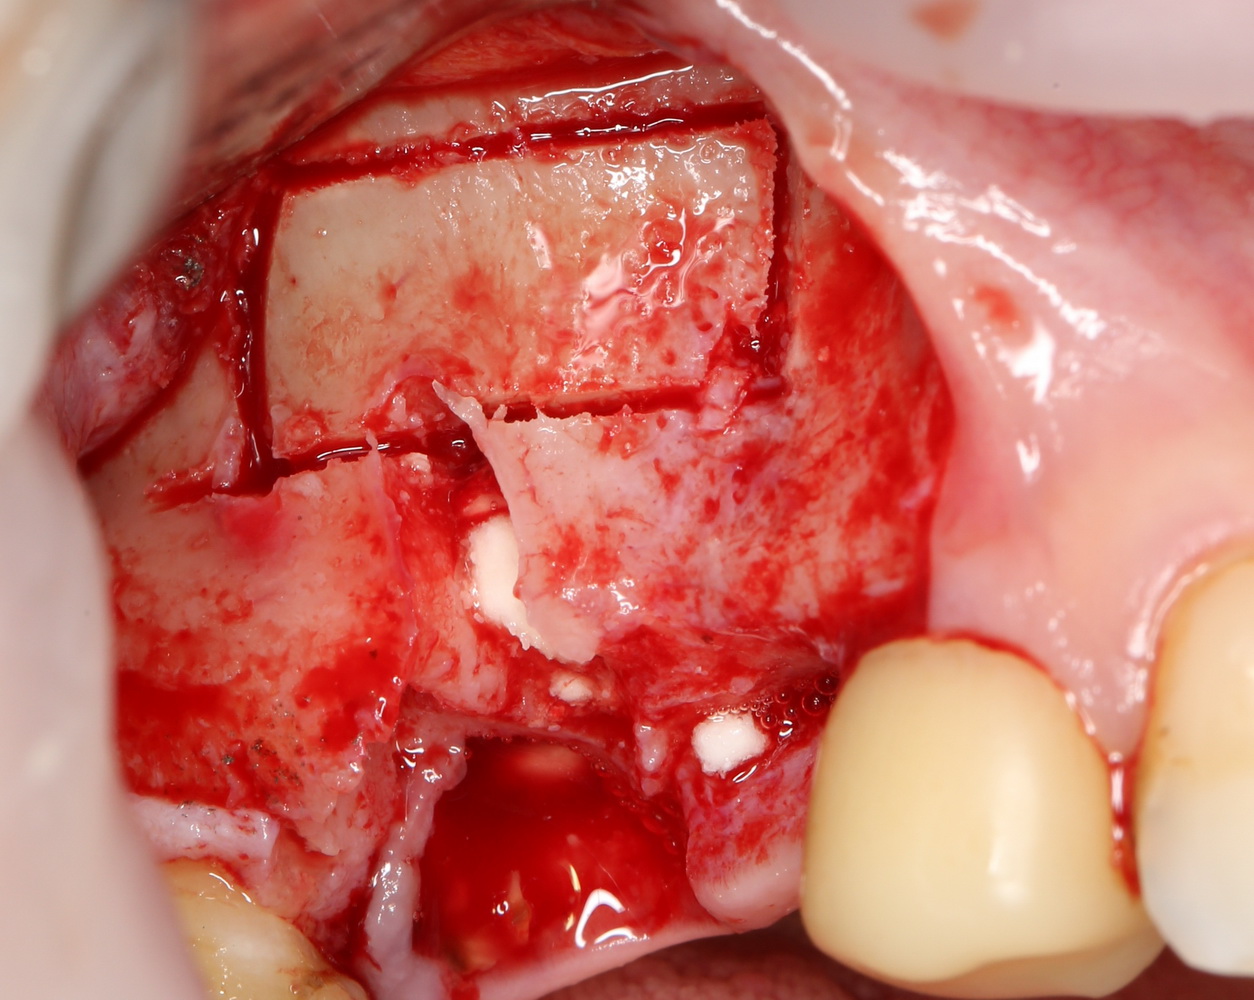

Синуслифтинг и остеопластика

В собственной клинической практике я нередко сочетаю синуслифтинг с увеличением объема альвеолярного гребня (аугментацией). Последнее может быть достигнуто методом аутотрансплантации (пересадки) костных фрагментов (рис 37, 38, 39):

Рисунок 37, 38, 39. Синуслифтинг с одномоментной аугментацией альвеолярного отростка методом аутотрансплантации костных фрагментов: слева – этап синуслифтинга, в центре – этап восстановления объема альвеолярного гребня аутокостным фрагментом, справа – установка имплантов через 3 месяца после синуслифтинга и остеопластики.

Либо комбинированной методикой с использованием барьерных мембран и остеопластических материалов (рис 40, 41, 42):

Рисунок 40, 41, 42. Синуслифтинг с одномоментной аугментацией альвеолярного отростка комбинированной методикой с использованием остеопластических материалов и барьерных мембран: слева – этап синуслифтинга, в центре – восстановление объема альвеолярного гребня с помощью остеопластических материалов, аутокостной стружки и барьерной мембраны, справа – установка имплантов через 3 месяца после синуслифтинга.

При этом, можно использовать костные фрагменты, полученные при создании доступа в верхнечелюстную полость (см рисунки 30 и 31). В случае необходимости воссоздания большого объема, можно использовать костные фрагменты, взятые из других донорских участков (угол и ветвь нижней челюсти, бугор и скуловой отросток верхней челюсти и т. д.).